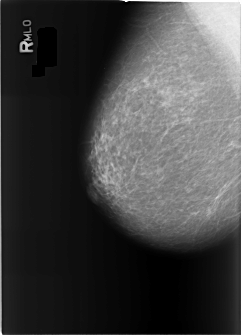

B_3368_1.RIGHT_MLO

RIGHT_MLO LINES 5680 PIXELS_PER_LINE 4112 BITS_PER_PIXEL 12 RESOLUTION 50 NON_OVERLAY